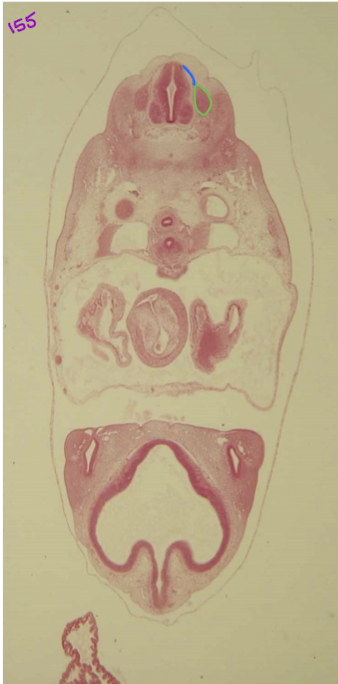

blue: dorsal root

green: dorsal root ganglion